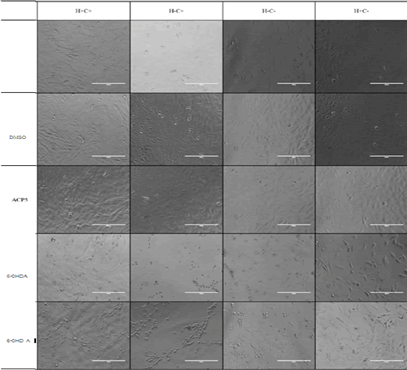

The different genotypes analyzed in this research were treated with 50 μM of the neurotoxin 6-OHDA and 0.5 μM of ADEP4 and ACP5. Then the cell viability was determined by MTT Assay. Cell viability showed a concentration dependent reduction in the viability level of the different genotypes (Figures 5A and 5B). Compared to the vehicle control (DMSO), cell viability was mainly reduced in the HtrA2 KO/CHOP genotype. Depletion of HtrA2 significantly increased the susceptibility to treatment with 6-OHDA (p<0.0001).

These results display a drug concentration dependent effect on the cell viability of the genotypes, indicating that depletion of cellular content might be due to high concentrations of drug treatment with 6-OHDA. Therefore, the concentration of the drug will be proportional to the number of living cells as shown in Figure 6.

ATP production was determined via ATP assay nominalized by the measurement of protein levels using the Bradford method. Likewise, in the cell viability assay, the ATP assay also displayed a concentration dependent reduction in energy production among the different genotypes and reflected both the cell viability and the metabolic status of the cells. The results illustrated that depletion of HtrA2 significantly increased susceptibility to drug treatment as shown in (Figure 7). Compared to the vehicle control (DMSO), the loss of energy production was significantly higher in the HtrA2 KO/CHOP genotype treated only with 6-OHD A (p<0.0001).

Journal-Neurological-Disorders-Microscopy

Figure 7. Microscopy visualization of mouse embryonic fibroblasts (MEFs) obtained from wild-type (WT), CHOP knockout (KO) and HtrA2 KO mice treated with 6-OHDA and ACP5. Compared to the other treatments, the HtrA2/CHOP KO genotype had a significantly lower concentration of live cells than the well treated with only ACP5, which significantly improved cell survival.